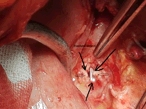

Retrieval of a retained video capsule endoscope with laparoscopic surgery

Sumita A Jain and others

Journal of Surgical Case Reports, Volume 2018, Issue 10, October 2018, rjy245, https://doi.org/10.1093/jscr/rjy245